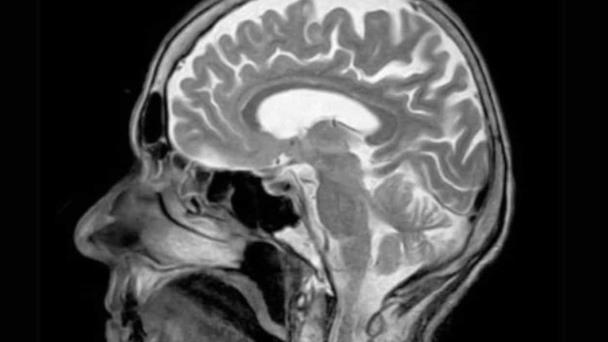

A través de un nuevo método de análisis cerebral expertos observaron que el cerebro funciona como un todo unificado y no por regiones aisladas como se llegó a creer. Investigadores de la Universidad de Duke confirmaron que el cerebro funciona como una red integrada e interdependiente, a través del uso de un método de medición, por el cual emplearon imágenes de resonancia magnética.